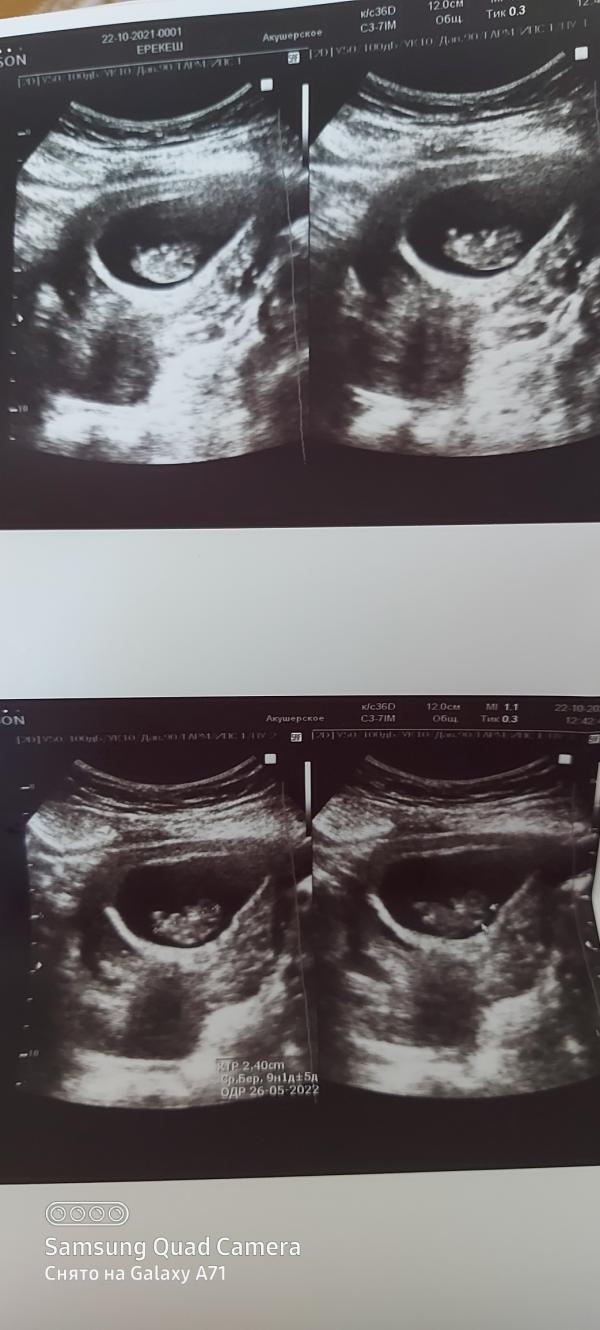

9 полных недель. Хотела дотерпеть до 12 недели для узи, но есть боли. Теперь к болям в животе, добавилась головная боль. Узист сказала, что не нравится образование в области затылка малыша моего.😪 прозвучала кистозная гигрома. Сказала не переживать, что нужно дождаться первого скрининга. Но как теперь успокоиться. Вот в чём вопрос. В первой беременности пугали большим твп, с тех пор никогда не переживала настолько как сейчас. Было ли у кого-то так же. Теперь 2 недели ожидания и чтение инфо с интернета не дадут покоя, чувствую.☹ дай Аллах, всё обойдётся. Все фото с узи на 9 неделе пересмотрела. Вроде, на мой непрофессиональный глаз, не вижу различий от моих снимков. Если есть в блоге врачи, взгляните, пожалуйста #первыйпост

По опыту ведения подопечных у малышей которых был такой же диагноз, обычно к 14-17 нед.гигрома уходила. И родились абсолютно здоровые детки.